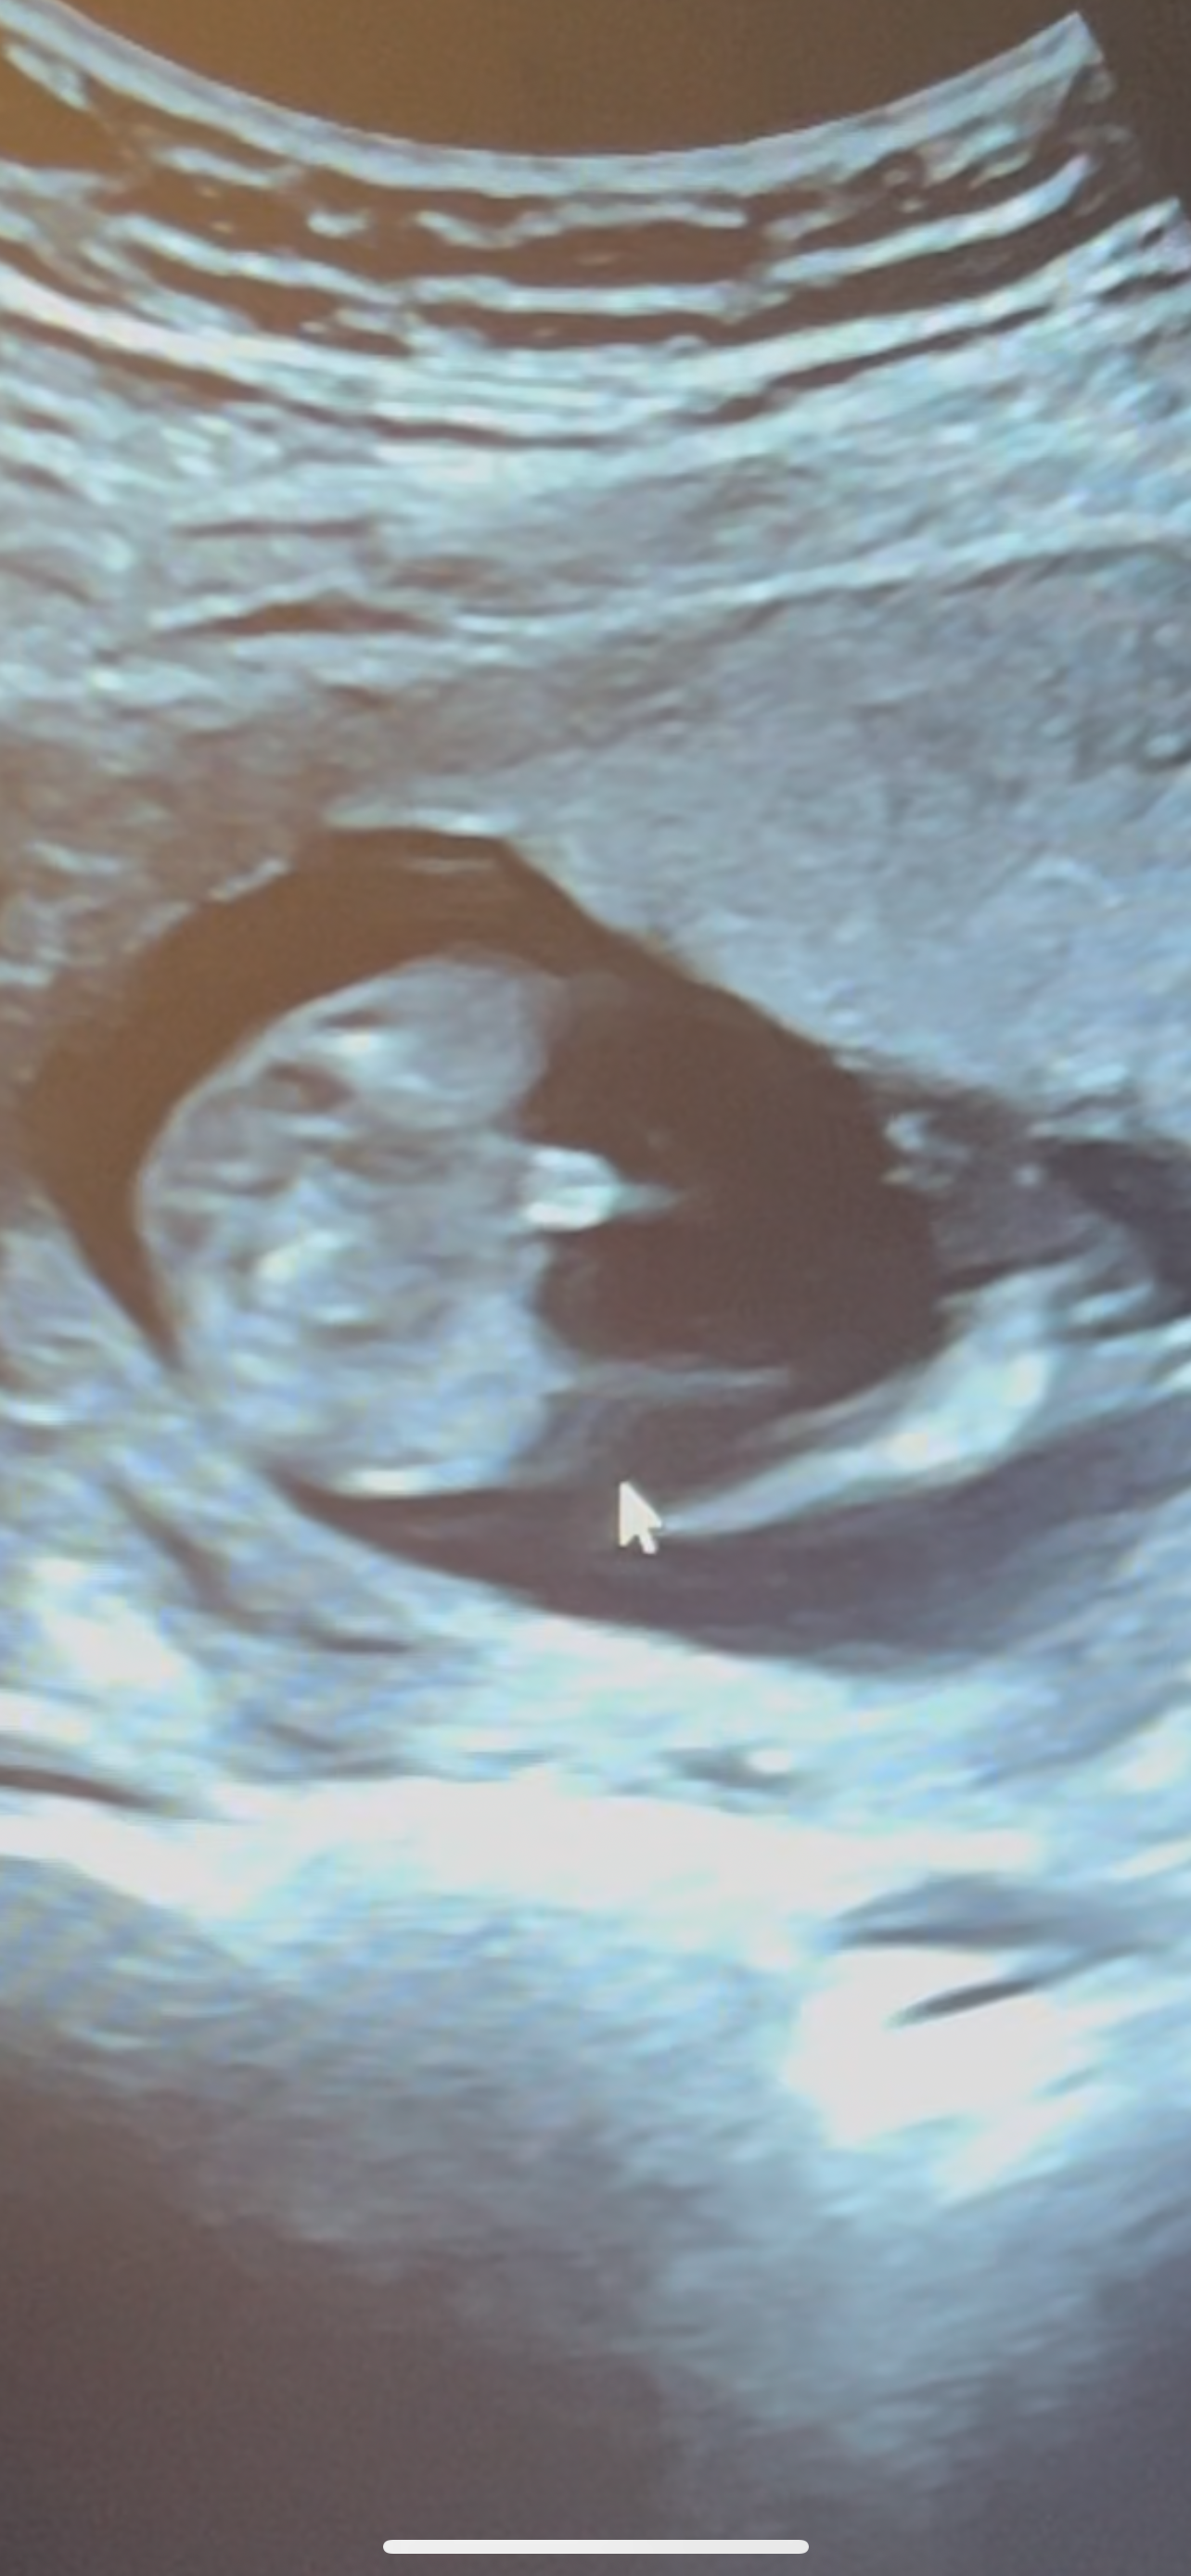

아들인것 같아용🌶️❤️

남편이 ㅋㅋㅋ 탯줄 아니냐고 하는데 ㅋㅋㅋㅋ 제눈엔.. 빼박...😂❤️🌶️❤️ 어때 보이시나용~?!